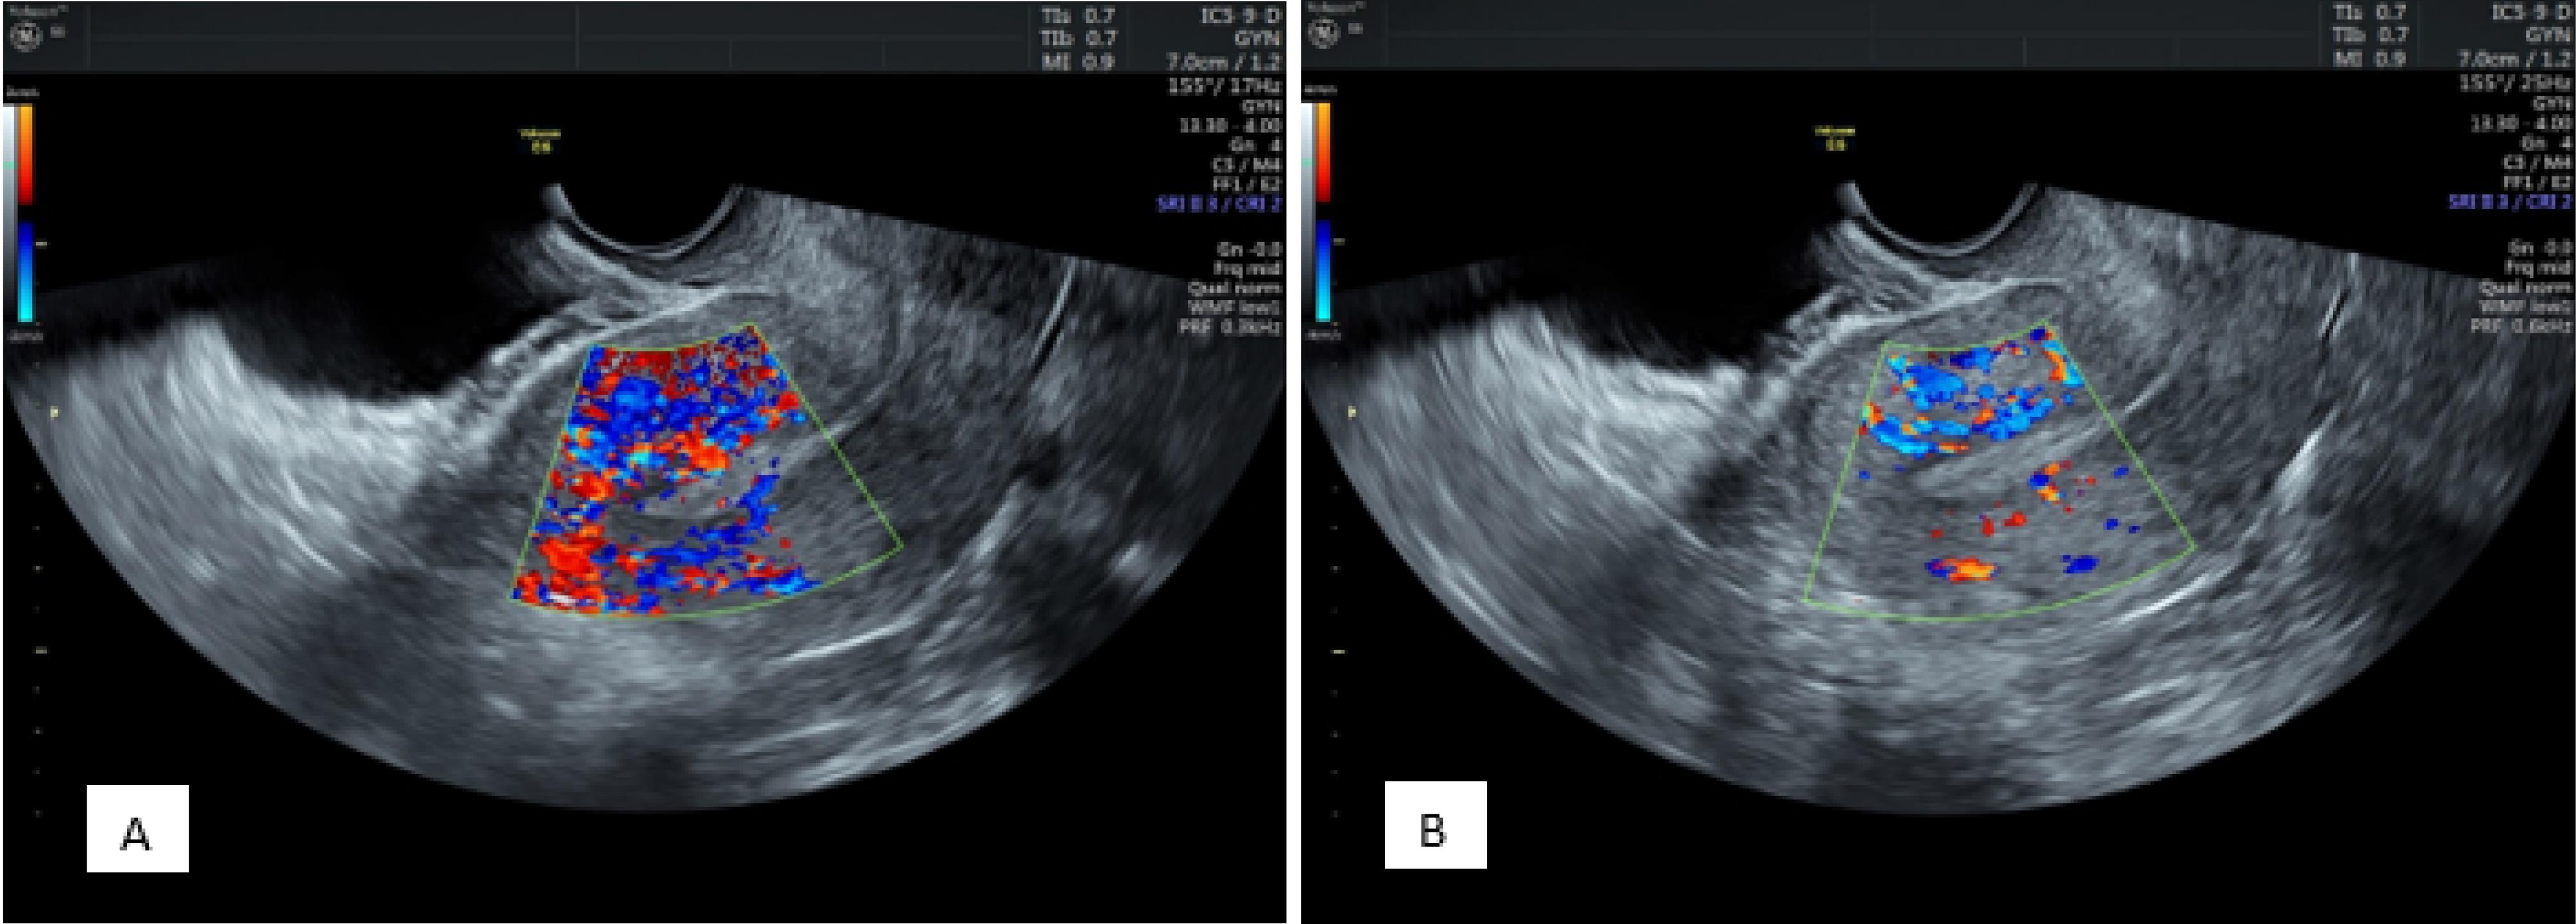

Endometrial Zone III Vascularity

According to the comparison results related to zone III vascularity distribution in patients before progesterone administration, multifocal distribution was observed in 166 patients, and sparse distribution was found in 34. After administration, multifocal distribution and sparse distribution were detected in 111 and 89 patients, respectively (P = 0.001).

As regards zone III vascularity distribution before progesterone administration in the positive pregnancy group, multifocal distribution and sparse distribution were found in 76 and 5 patients, respectively. In the negative pregnancy group, multifocal distribution was observed in 90 patients, and sparse distribution was detected in 29 patients (P = 0.001).

Concerning zone III vascularity distribution after progesterone administration in the positive pregnancy group, both types of distribution were found in 56 (multifocal distribution) and 25 (sparse distribution) patients, respectively. In the negative pregnancy group, multifocal distribution and sparse distribution were observed in 55 and 64 patients, respectively (P = 0.001, Figure 3).

Figure 3.

Endometrial Zone III Vascularity Distribution Before (A) and After (B) Progesterone 9 Administration Demonstrating a Decrease in Multi-focal Distribution and the Sparse Vascularity Being 10 More Prominent